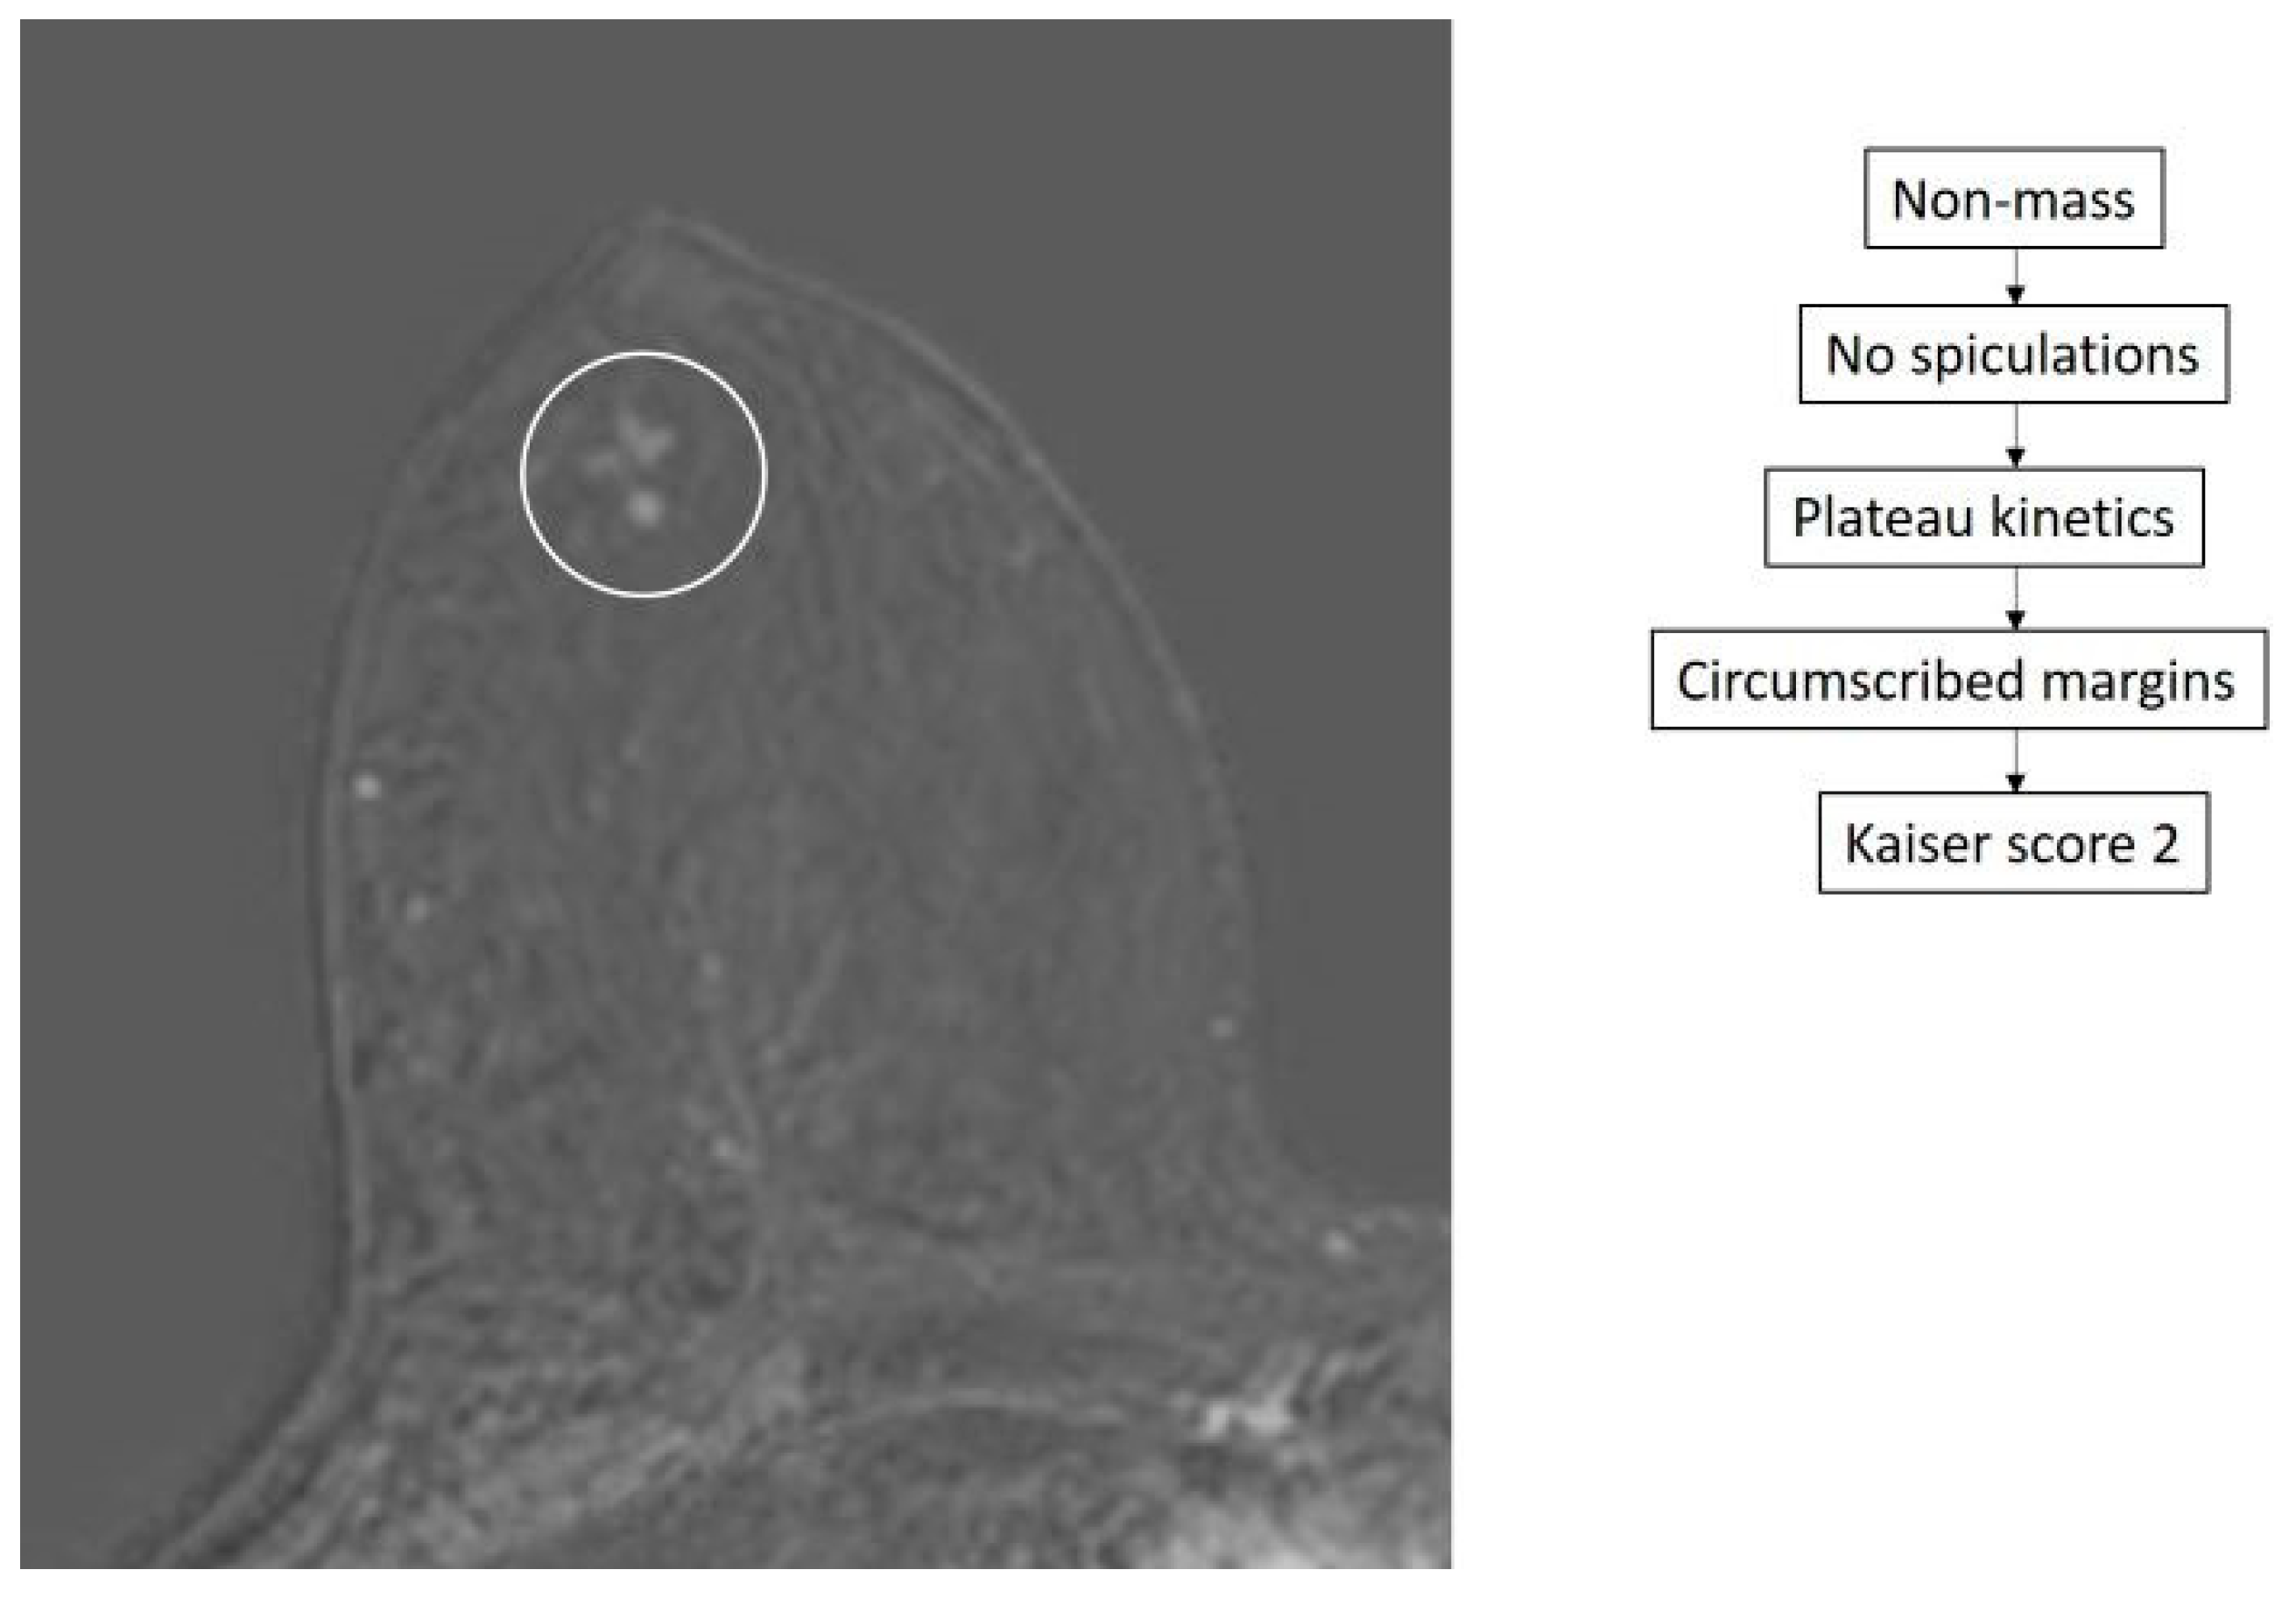

- Dietzel, M.; Baltzer, P.A.T. How to Use the Kaiser Score as a Clinical Decision Rule for Diagnosis in Multiparametric Breast MRI: A Pictorial Essay. Insights Imaging 2018, 9, 325–335. [Google Scholar] [CrossRef] [PubMed]

- Baltzer, P.A.T.; Krug, K.B.; Dietzel, M. Evidence-Based and Structured Diagnosis in Breast MRI Using the Kaiser Score. ROFO. Fortschr. Geb. Rontgenstr. Nuklearmed. 2022, 194, 1216–1228. [Google Scholar] [CrossRef]